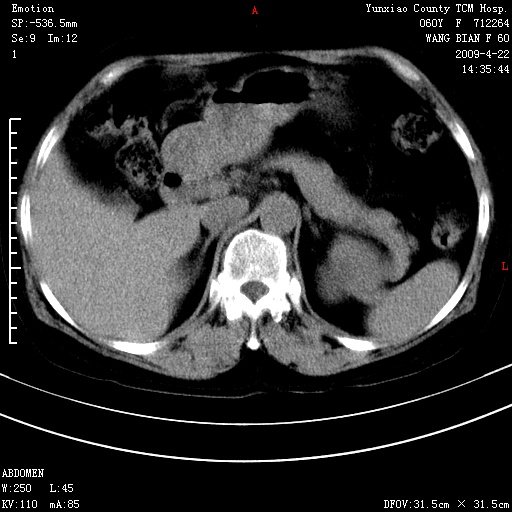

蛛网膜颗粒压迹 左肾低密度影囊肿可能。

不出外肾癌,强化下看

2、左肾囊肿。

脑正常,肾有事,须强化,再定性.

1、头颅未见明显异常。2、左肾囊肿可能。建议增强

1、枕骨蛛网膜粒压迹。2、左肾囊肿可能。建议增强

头颅未见明显异常。左肾囊肿。

1)枕骨蛛网膜粒压迹。2)左肾囊肿可能。

脑正常,肾有事,须强化,再定性

不出外肾癌,强化下看,枕骨蛛网膜粒压迹。

2、左肾囊肿可能性大。